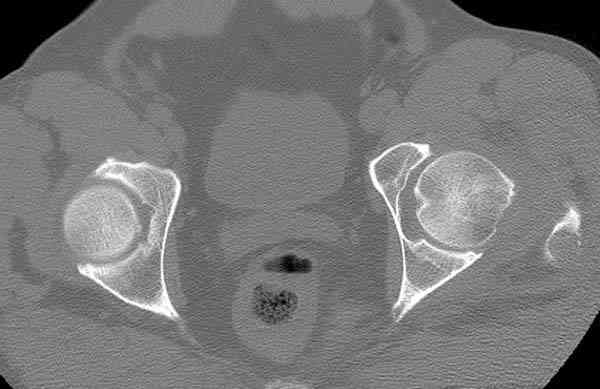

Здесь представлены снимки больного 65 лет, поступившего с диагнозом перелом

бедра после автоаварии.

На второй день (7) обнаружен пропущенный перелом,

сделаны Компьютерная Томограмма